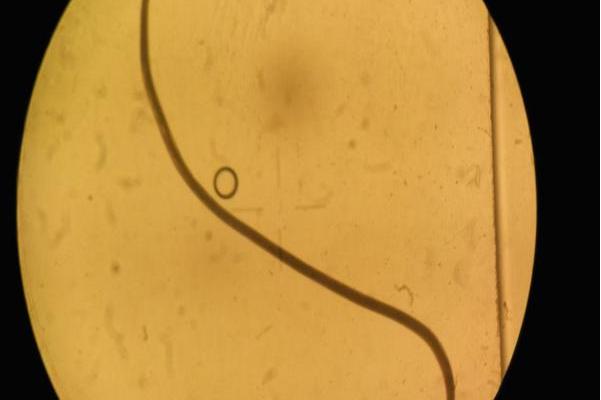

辐射食道口线虫

棘颚口线虫